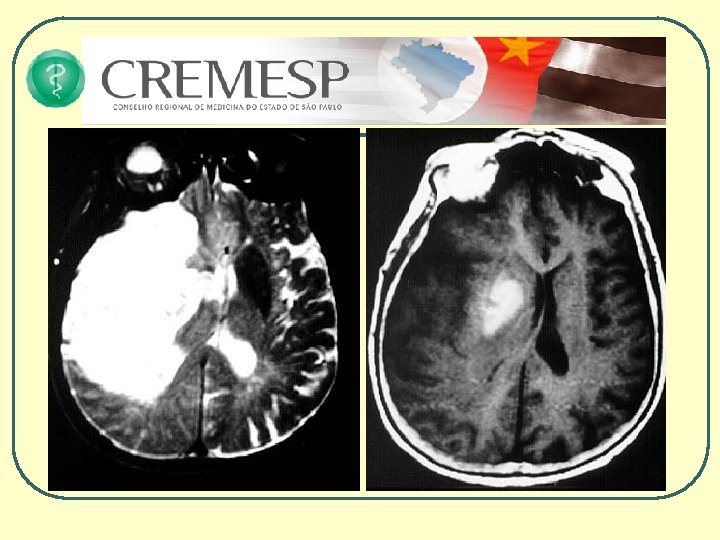

AVCI há 3 horas

AVCI há 48 horas

CT - Sangue